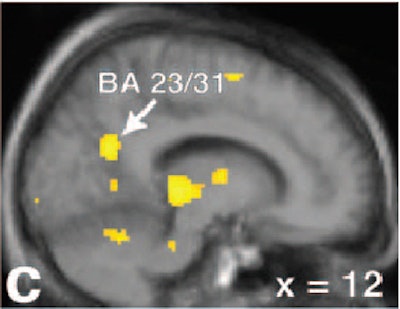

| Regional activation maps. Activation contrast for the couples stimuli versus fixation (a-c, above) and the couples stimuli versus neutral contrast (d-f, below). Left, coronal image (a) showing greater bilateral amygdala and hypothalamic activations for males versus females for the couples versus fixation contrast. Couples versus fixation contrast for males, at the same coronal and axial views (b). The same contrast and views for females (c). |

According to the results, men had greater neural responses in the bilateral amygdala and hypothalamus than did women in response to images of the couples engaged in sexual activity (p<0.001). Those same images also produced greater activations in the left amygdala, and marginally greater activations in the right amygdala and hypothalamus, in men than in women (p<0.001). Additionally, men showed greater focal differential activations at a lower statistical threshold in both sides of the amygdala (p<0.005), as well as in the hypothalamus, bilateral posterior thalamus, and left hippocampus.

Finally, there was some overlap in response between the sexes, most notably in the bilateral parieto-temporal region (visual processing, somatosensory function) and the anterior cingulate (emotion, sexual motivation).